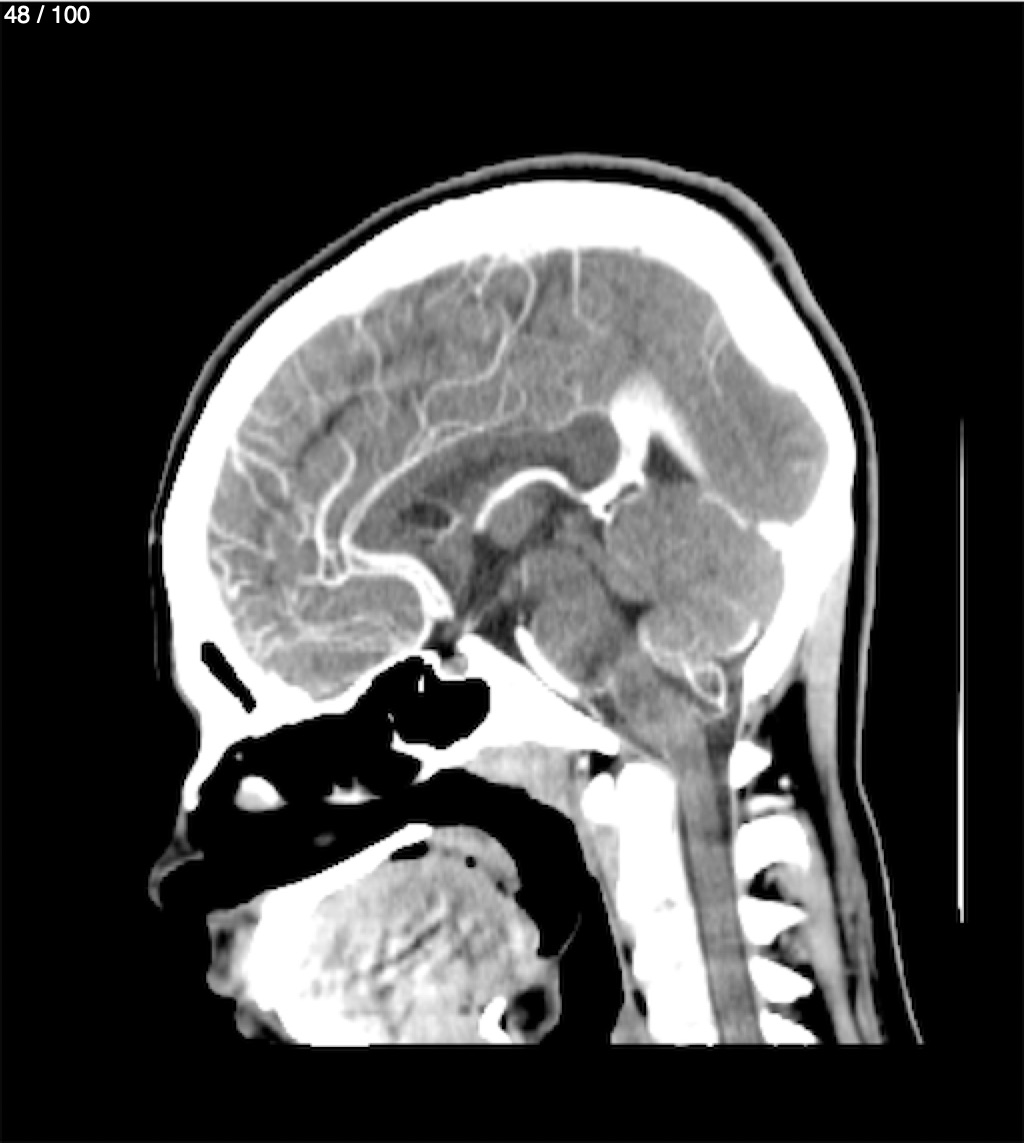

Fernando Daniel Gutierrez Caraba - Tc. Craneo Syc